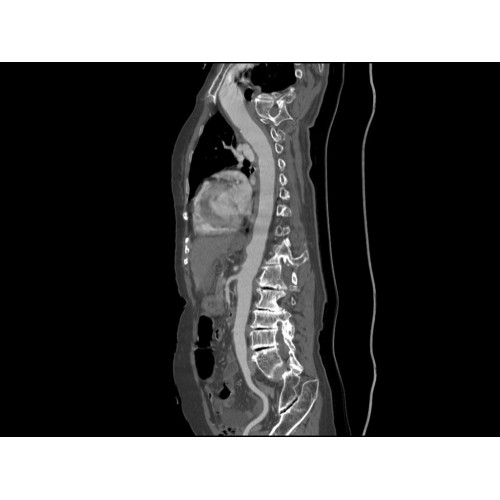

Позволяет проводить комплексные исследования всех анатомических зон, включая нейровизуализацию, ангиографию, исследования органов грудной и брюшной полости. Особенно эффективен для раннего выявления онкологических заболеваний.

Обеспечивает высокую точность при кардиологических исследованиях, визуализации костных структур и суставов. Подходит для динамического наблюдения в ходе лечения.